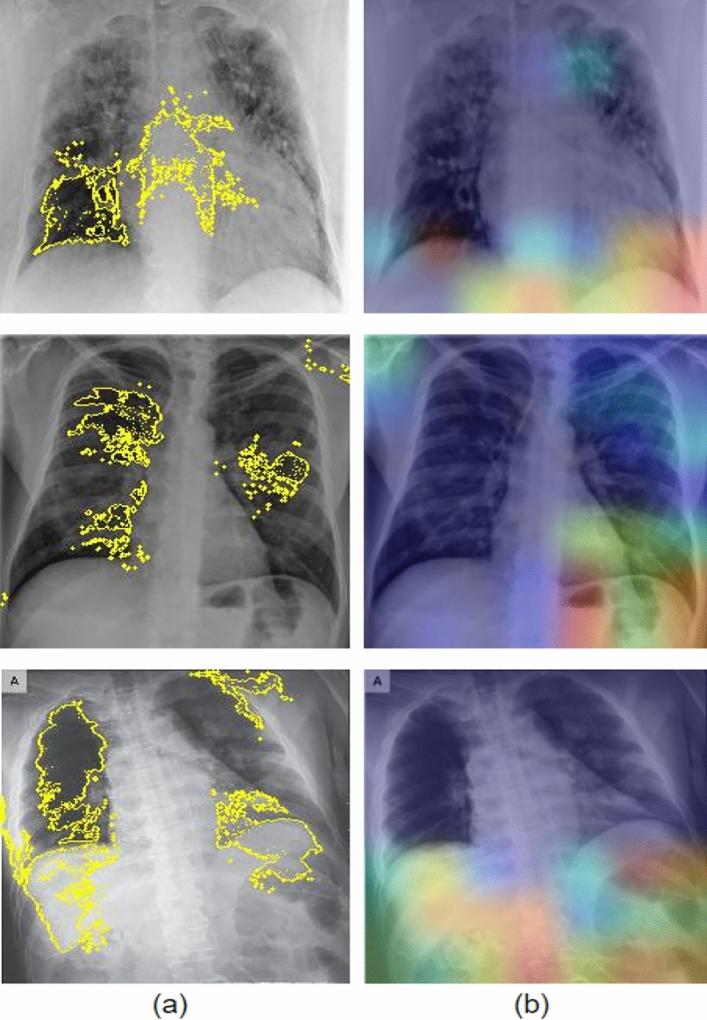

COVID-19 has been a global pandemic. Flattening the curve requires intensive testing, and the world has been facing a shortage of testing equipment and medical personnel with expertise. There is a need to automate and aid the detection process. Several diagnostic tools are currently being used for COVID-19, including X-Rays and CT-scans. This study focuses on detecting COVID-19 from X-Rays. We pursue two types of problems: binary classification (COVID-19 and No COVID-19) and multi-class classification (COVID-19, No COVID-19 and Pneumonia). We examine and evaluate several classic models, namely VGG19, ResNet50, MobileNetV2, InceptionV3, Xception, DenseNet121, and specialized models such as DarkCOVIDNet and COVID-Net and prove that ResNet50 models perform best. We also propose a simple modification to the ResNet50 model, which gives a binary classification accuracy of 99.20% and a multi-class classification accuracy of 86.13%, hence cementing the ResNet50's abilities for COVID-19 detection and ability to differentiate pneumonia and COVID-19. The proposed model's explanations were interpreted via LIME which provides contours, and Grad-CAM, which provides heat-maps over the area(s) of interest of the classifier, i.e., COVID-19 concentrated regions in the lungs, and realize that LIME explains the results better. These explanations support our model's ability to generalize. The proposed model is intended to be deployed for free use.

新冠疫情已成为一场全球大流行疾病。要实现“曲线平缓”需要进行密集检测,而全球一直面临检测设备短缺以及缺乏专业医疗人员的问题。因此有必要实现检测过程的自动化并提供辅助。目前有多种诊断工具被用于新冠病毒检测,包括X光和CT扫描。本研究聚焦于通过X光检测新冠病毒。我们探讨两类问题:二分类(新冠病毒感染和未感染)和多分类(新冠病毒感染、未感染以及肺炎)。我们研究并评估了几种经典模型,即VGG19、ResNet50、MobileNetV2、InceptionV3、Xception、DenseNet121,以及诸如DarkCOVIDNet和COVID-Net等专门模型,并证明ResNet50模型表现最佳。我们还对ResNet50模型提出了一项简单修改,其实现了二分类准确率达99.20%,多分类准确率达86.(此处有误吧,按原文应为86.13%)13%,从而巩固了ResNet50在新冠病毒检测以及区分肺炎和新冠病毒感染方面的能力。所提出模型的解释通过LIME(提供轮廓)和Grad-CAM(在分类器的感兴趣区域提供热图,即肺部新冠病毒集中区域)进行解读,并且发现LIME能更好地解释结果。这些解释支持了我们模型的泛化能力。所提出的模型旨在免费部署以供使用。